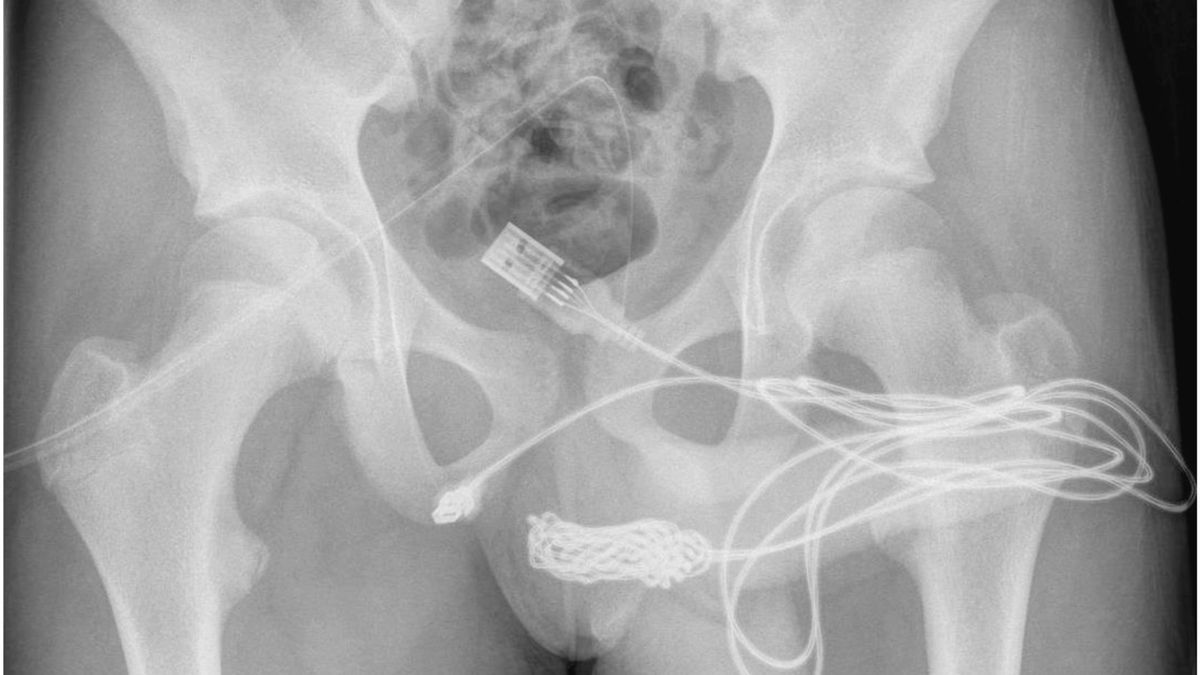

ब्रिटेन में एक 15 साल के लड़के को यूएसबी केबल से अपने प्राइवेट पार्ट की लंबाई नापने में दिक्कत हुई। ऐसा करने से युवक पर भारी असर पड़ा लेकिन डॉक्टरों ने एक जटिल ऑपरेशन कर उसकी जान बचा ली। प्राप्त जानकारी के अनुसार, उसने यौन प्रयोग के दौरान मूत्रमार्ग में केबल डालने की बात स्वीकार की, ताकि अंदर की लंबाई का पता लगाया जा सके।

इसके साथ ही केबल के अंदर फंसने से यूरिनल ट्यूब से खून बहने लगा। उसने केबल हटाने की कोशिश की लेकिन दर्द असहनीय था।बेटे को दर्द होने पर मां बेटे को अस्पताल ले गई। ट्यूमर के आकार के कारण डॉक्टर धातु की छड़ से केबल नहीं निकाल पा रहे थे, इसलिए लड़के की सर्जरी करवाई गई। फंसे हुए केबल तक पहुंचने के लिए उसके जननांगों और गुदा के बीच एक कैथेटर डाला गया था।

बेहद जटिल प्रकार की सर्जरी कर युवक को बचा लिया गया।नई बात यह थी कि मरीज मानसिक रूप से फिट था, पहले ऐसा कोई विकार नहीं देखा गया था। उसने इसे सिर्फ जिज्ञासा से किया लेकिन परिणामों के बारे में नहीं सोचा। यह घटना नवंबर 2021 में हुई थी, जिसे पहली बार यू.एस. द्वारा हाल ही में साइंस डायरेक्ट रिपोर्ट में प्रकाशित किया गया था। ऐसा मिरर की रिपोर्ट में कहा गया है।